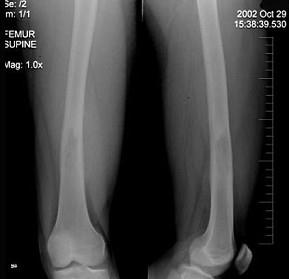

问题 23岁男性患者,因右股骨下段肿胀、疼痛伴发热2月,来科行X线检查,其影像征象如示,最可能的诊断是 ( )

选项 A、组织细胞增生症 B、骨肉瘤 C、溶骨性骨肉瘤 D、Ewing氏肉瘤 E、急性化脓性骨髓炎

答案 D